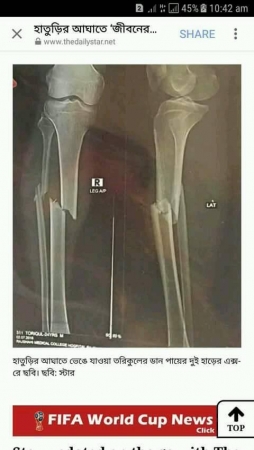

অনন্য দায়িত্বশীল আমি বলেছেন: এটা হলো হাতুড়ী মামুনের আঘাতে তরিকুলের ছিন্ন হওয়া মেরুদন্ড ও পা।